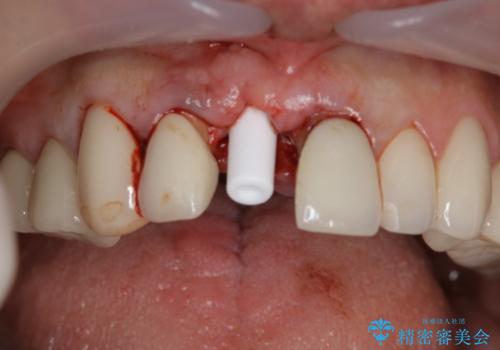

患者様のご要望もあり、審美性の確保ができる抜歯早期埋入→埋入後即時荷重という手術法を取りました。

近年、インプラントの素材や手術法の研究が進み、保存不可能となった歯牙に対して抜歯してすぐインプラントを埋入し、さらに直後から仮歯がを入れ噛むことができる【抜歯即時埋入】【即時荷重】という技法が確立されました。

それと比較すると、今回の方法では骨にしっかりと固定されているインプラントに単独で仮歯を装着することができるためフロスも通せますし、ある程度負荷のかかる食事も気にせずできるようになります。

- 税込¥341,000- (インプラント本体+仮歯用土台+仮歯+早期埋入,即時荷重技術料)費用は治療当時の料金となります